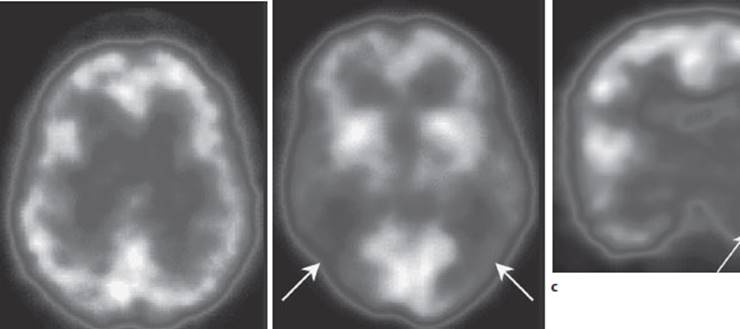

Fig. 4.13 SPECT studies. a Normal study. b SPECT in a patient with Alzheimer disease. Hypoperfusion is seen bilaterally in the parietal and temporal lobes, particularly on the right. Cf. normal finding in a. c This SPECT study in a patient with medically intractable complex partial seizures, performed after the intravenous administration of 180 MBq of 133l-iomazenil, reveals diminished binding to benzodiazepine receptors in the left temporal region.

Indications. SPECT can be performed to demonstrate reduced perfusion of the brain, e.g., in stroke or in Alzheimer disease, which is associated with reduced activity in the temporoparietal region (Fig. 4.13a, b). It can also be used to detect focal pathological processes of other kinds, e.g., epileptogenic foci (Fig.4.13c).